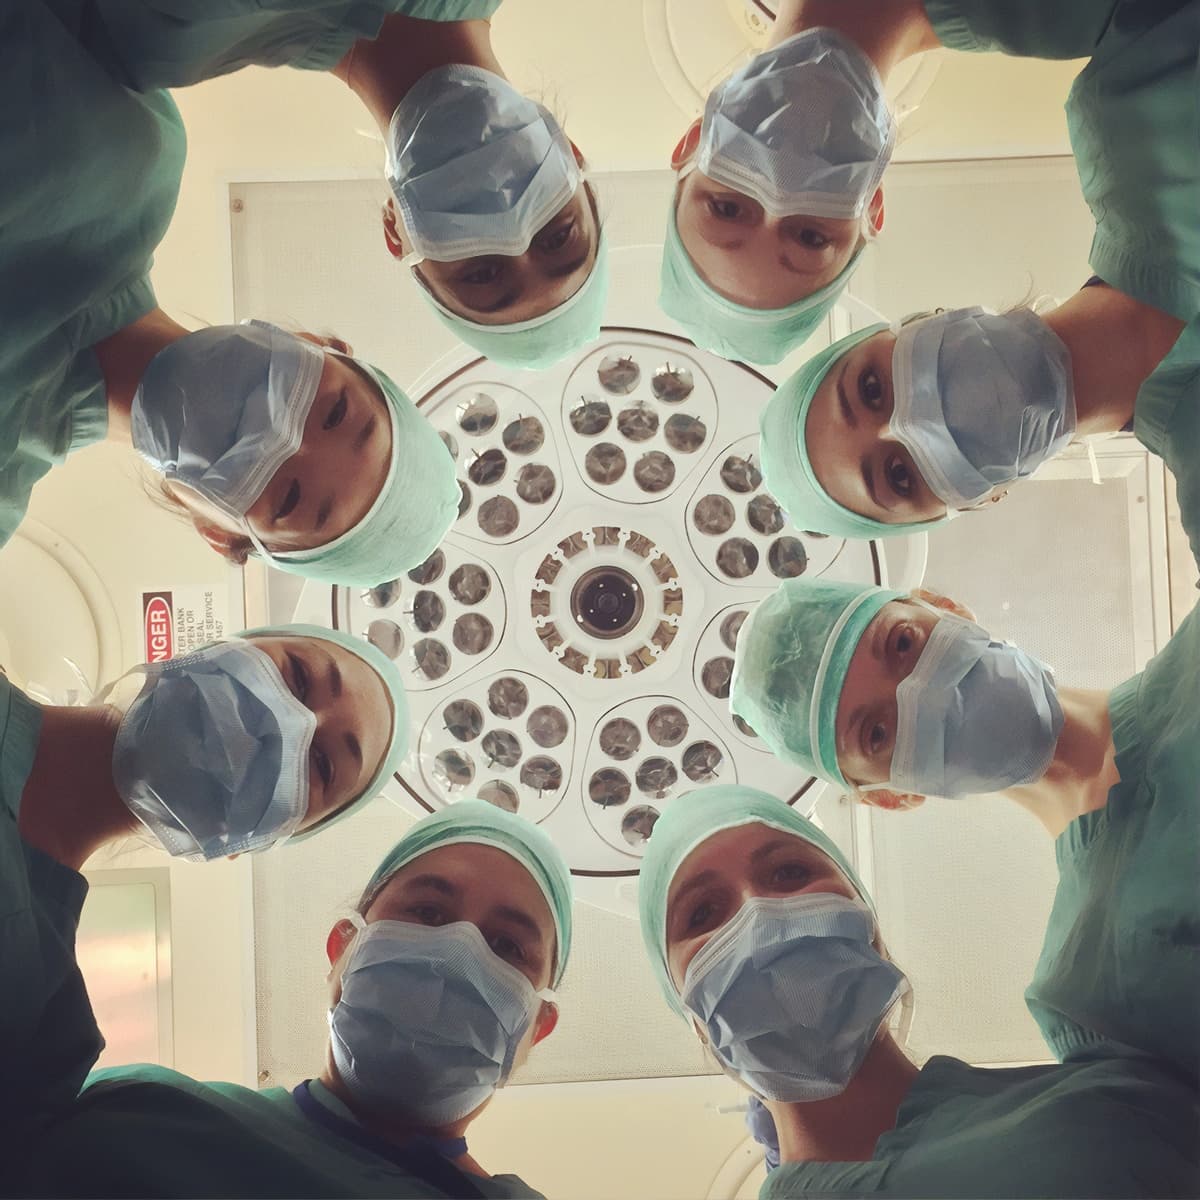

Lotaria, cobaias & muitas incertezas: a perturbadora leitura do parecer 17

PÁGINA UM divulga em exclusivo o teor integral dos 23 pareceres da Comissão Técnica de Vacinação contra a Covid-19

Remdesivirgate: um negócio de 20 milhões de euros e de lobbies associados à Ordem dos Médicos